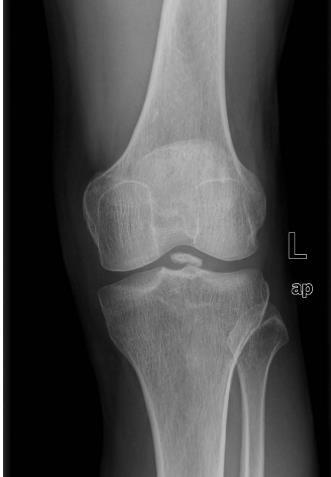

关节内游离体是骨科的常见病。由于关节腔是一个***的封闭腔隙,一旦关节内产生游离体,则会在关节腔内到处走动,犹如老鼠一样,所以关节内游离体也称为关节鼠。游离体可以发生在人体的所有关节内,但以膝关节最常见。

游离体特点:多少不等,大小不一,形态各异。

主要依靠患者的临床症状、体格检查、影像学检查及膝关节镜检查等。